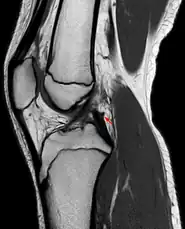

Posterior meniscofemoral ligament on MRI, sagittal